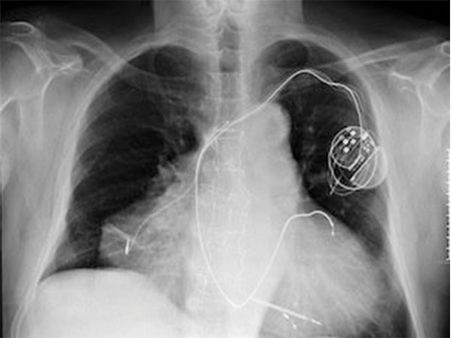

A Man With Two Hearts!

This Italian man was all normal when he was born. However, he developed this condition due to a surgery. Doctors found out about his condition when he was admitted for a cardiac arrest. Luckily, this man survived even after having two heart attacks as well!